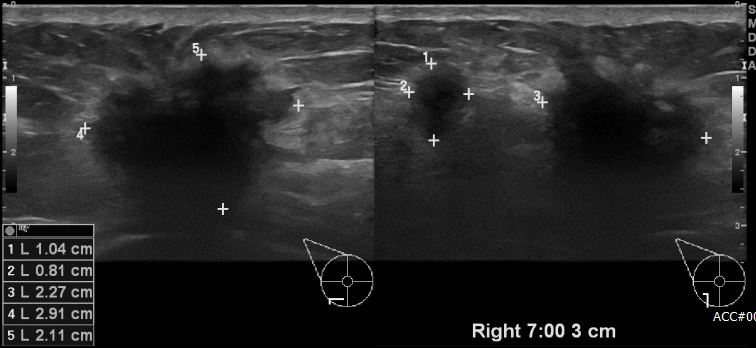

상기환자 유방에 만져지는 멍울로 내원하신 40대 여성분으로 우측 7시 방향에서 3cm 떨어진 거리의 만져지는 멍울 조직검사 시행하여 우측 침윤성 유관암 진단 되었습니다.